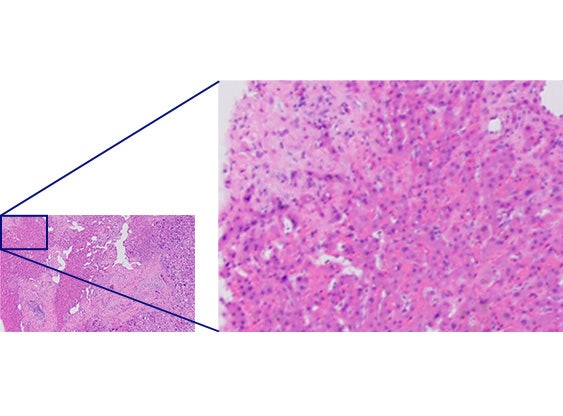

Imágenes mejoradas para aplicaciones de investigación clínica

La mejora de la planitud, la apertura numérica y la aberración cromática permiten obtener imágenes claras en alta resolución con una excelente reproducción de los colores. El control de la aberración cromática superior de los objetivos ofrece una precisión de los colores mejorada en todo el espectro. La eliminación de la aberración del color violeta crea blancos claros y rosas vivos, mejorando el contraste y la nitidez. La corrección de la aberración cromática, en un amplio rango de longitudes de onda (400-1000 nm), le permite adquirir imágenes en varios colores de alta resolución durante la observación por fluorescencia, como el análisis por hibridación fluorescente in situ (FISH, siglas en inglés).